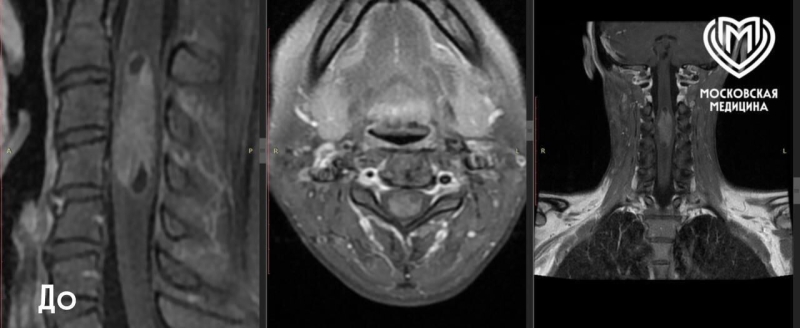

Отмечается, что благодаря исследованию выяснилось, что у пациентки эпендимома — одна из редких опухолей у взрослых. Такие опухоли способны метастазировать по нервной системе, маскируясь под самые разные неврологические болезни.

«Мы провели исследование и выявили интрамедуллярную опухоль спинного мозга протяженностью около шести сантиметров — женщине нужна была операция. В нейрохирургическом отделении пациентке удалили опухоль под микроскопом с интраоперационным нейрофизиологическим мониторингом — во время операции специалисты контролировали проводимость и чувствительность», — рассказал Дмитрий Вакатов, заведующий нейрохирургическим отделением №49, чьи слова приводятся в сообщении.

«В подобных случаях мы обязательно используем комплексную визуализацию: МРТ и МРТ-трактографию, что позволяет построить детальную карту проводящих путей. Это существенно снижает риск неврологического дефицита», — добавил врач.